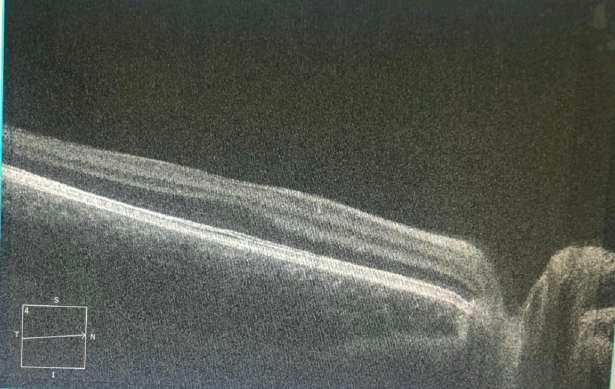

Caso aportado por Dr. Álvaro Rodríguez

Imagen A

üPigmento en Cápsula anterior

üQuemosis conjuntival 360ª

üHerida penetrante iridiana

üHerida penetrante corneal

Imagen B: sección óptica de la córnea fotografiada lateralmente